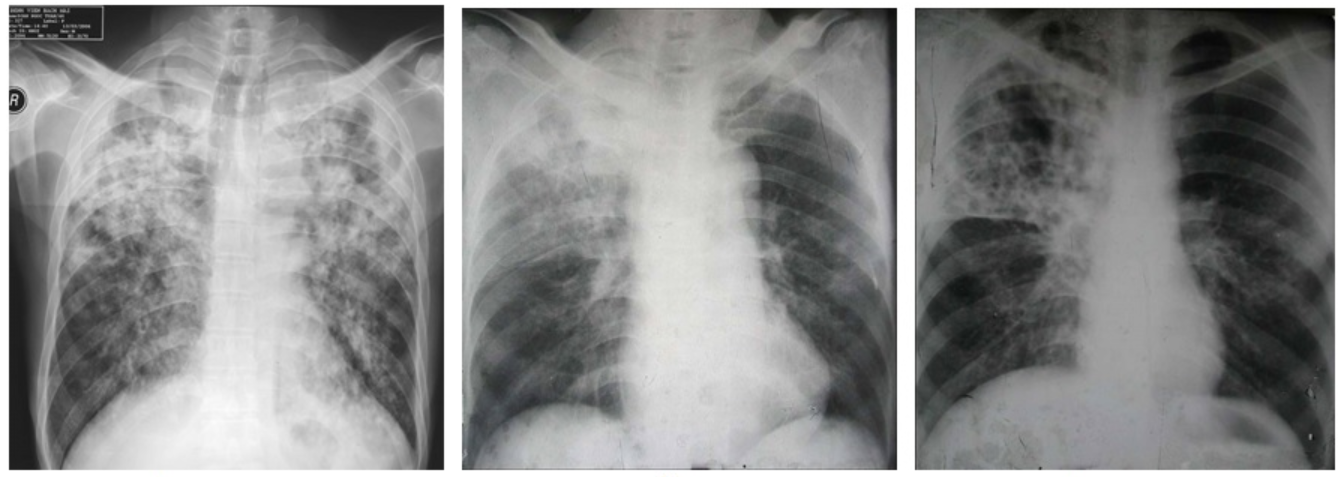

Trẻ nhỏ mắc bệnh lao phổi và lao thanh quản ít lây nhiễm bệnh trong cộng đồng hơn người lớn. Điều này, là do trẻ thường ho khan, ít có đờm. Tuy nhiên, trẻ vẫn có khả năng lây nhiễm. Trẻ em cũng được đánh giá khả năng lây nhiễm dựa trên các tiêu chí như người lớn. Những tiêu chí này bao gồm: Ho kéo dài 3 tuần hoặc lâu hơn, phát hiện đám vi khuẩn lao trên X quang ngực, mắc bệnh đường hô hấp có liên quan đến phổi, thanh quản.

Người mắc bệnh lao có khả năng lây nhiễm vi khuẩn cho người khác. Xét nghiệm đờm AFB và nuôi cấy vi khuẩn nên được sử dụng để xác định bệnh.

- Có áp xe hoặc tổn thương mở trong khi nồng độ vi khuẩn lao cao, đặc biệt là lây nhiễm qua dẫn lưu từ áp xe hoặc tổn thương rộng, hoặc nếu chất lỏng thoát nước là khí dung. Những người bị tràn dịch màng phổi do lao có thể bị lao phổi tiềm ẩn được che dấu trên X quang phổi vì tràn dịch màng phổi.